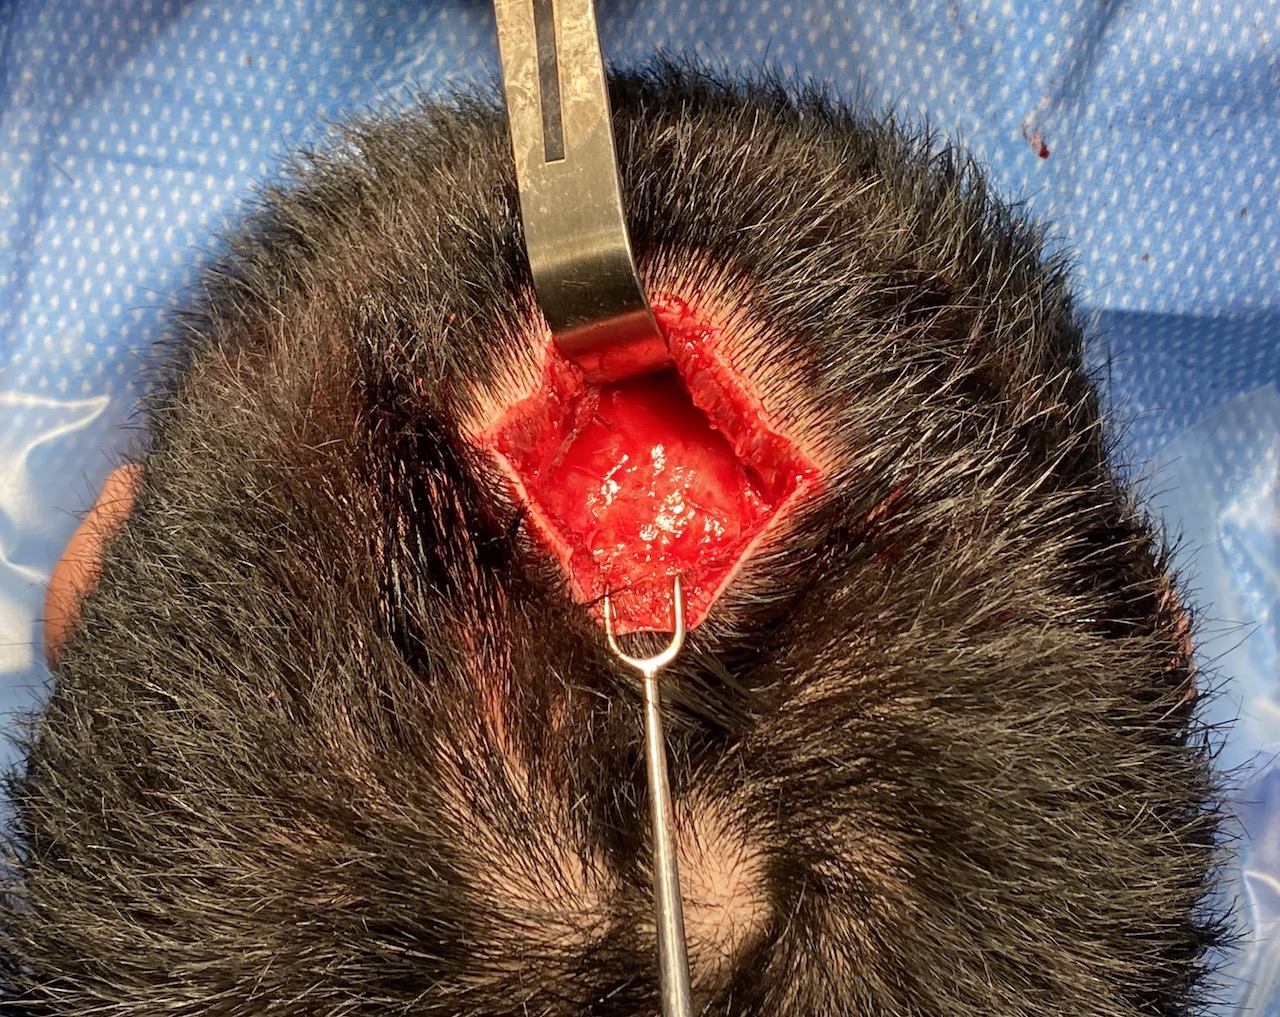

Desire for reduction of prominent occipital knob deformity.

Intraoperative result from occipital knob skull reduction through a direct small scalp incision.

Desire for reduction of prominent occipital knob deformity.

Intraoperative result from occipital knob skull reduction through a direct small scalp incision.